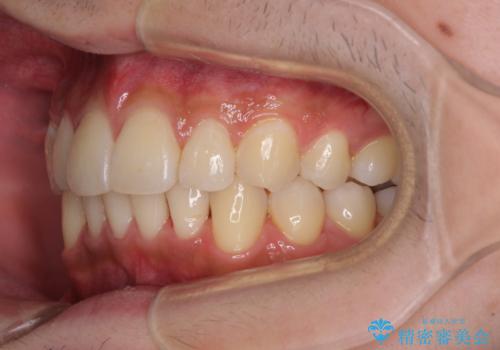

- 患者様

- 30代男性

- 矯正装置

- インビザライン・ライト

- 治療期間

- 9ヶ月

- 治療回数

- 5-10回

矯正治療後は、再度後戻りすることを極力回避するために、下顎前歯の舌側を細いワイヤーを用いて保定することとしました。